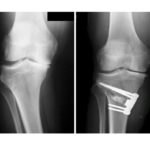

Radiographic Criteria for Optimum TKR

Courtesy: Dr S Macdonald, Ashok Shyam TV, Ortho Don’t Forget Pre-Operative Evaluation Before analyzing a painful postoperative knee, always revisit: Was TKA truly indicated? Was there clear bone-on-bone osteoarthritis? Could pain have originated elsewhere (e.g., hip)? Key Clinical Lesson Mild radiographic knee arthritis + severe hip arthritis ? knee replacement will not solve the pain. […]